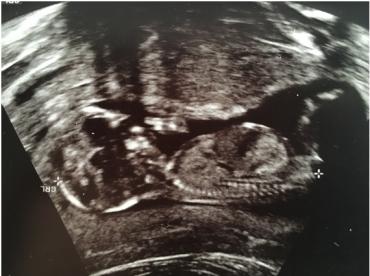

If it isn't the nub what It is?

Attachment 35580